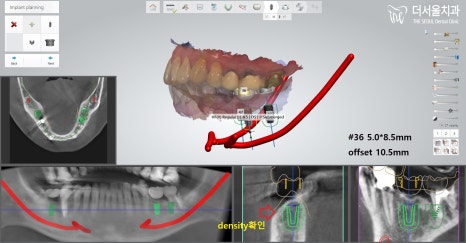

『분석에 들어갑니다.』

더서울 문정동치과 에서

컴퓨터 분석 프로그램을 이용하여

올바른 위치에 알맞은 각으로

식립할 수 있도록

수술 계획을 꼼꼼히 수립했습니다.

그런데 치아를 상실한지

좀 오래 되었기에 뼈소실이 있었습니다.

그런데 37번 어금니 자리는

치근 염증으로 인한 골소실이 있었고,

추후에 염증 제거 후,

뼈이식을 해줘야 되는 상황이었습니다.

수술 전 조심해야될 사항들을

하나씩 꼼꼼히 체크 후,

픽스처 식립 후 3D CT로

잘못 심어진 것은 없는지,

올바른 위치에 계획했던 대로

잘 심어졌는지 확인합니다.

별다른 문제없이 잘 심어졌군요. ^^